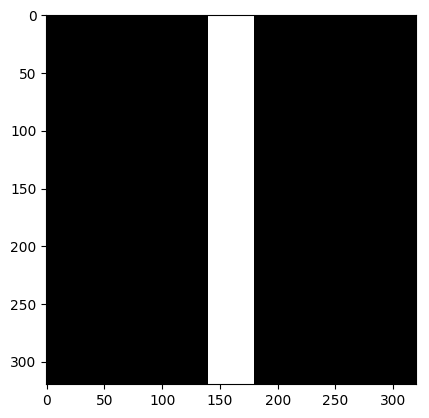

We consider the following two inverse problems: (i) Superresolution (SR), consisting of reconstructing a sharp image from measurements containing only the central low frequencies obtained by using the mask as in Fig. 2 (a & c); and (ii) Dealiasing, in which the obtained mask results in an aliasing artifact due to a coarser sampling in the phase-encoding direction. We use the masks displayed in Fig. 2(b & d). The inverse problem consists of restoring a finer sampling grid in the phase-encoding direction. Throughout the paper, we denote the experiments specifying the task name (one of the two tasks above) and the acceleration factor.

| (a) SR 4 | (b) Dealiasing 4 | (c) SR 8 | (d) Dealiasing 8 |